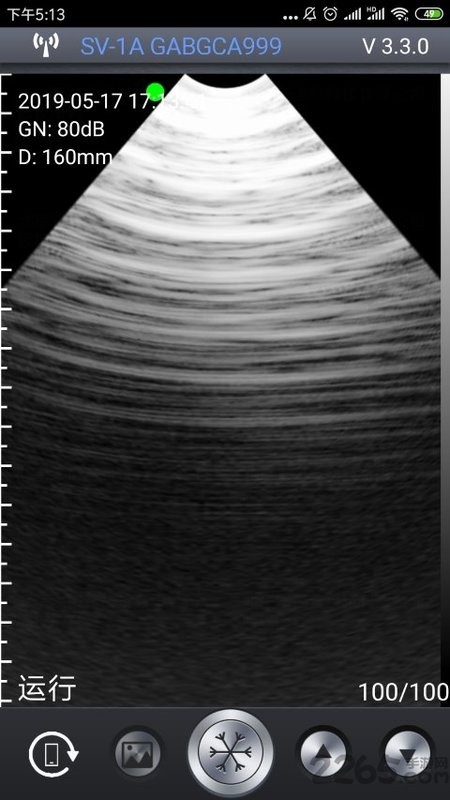

5、图片成像:

通过最强大的成像功能也是能让你查看到最全面的重要信息内容,任何图片信息都能够以最全面的方式为您介绍;

智能b超手机版是一款针对养殖业提供的b超检测工具,通过连接设备,手机拍摄的方式,展示图像信息,即时进行b超诊断,随时查看诊断数据,一目了然,轻松了解,操作简单,有助于解决各种各样的养殖问题,便于养殖人进行养殖工作!

智能B超 App与北京索诺普科技开发的无线兽用B超仪一起构成一套方便,高效的养殖业B超诊断系统。无线智能B超,是养猪人的绝佳工具,为您开启轻松工作的一天。